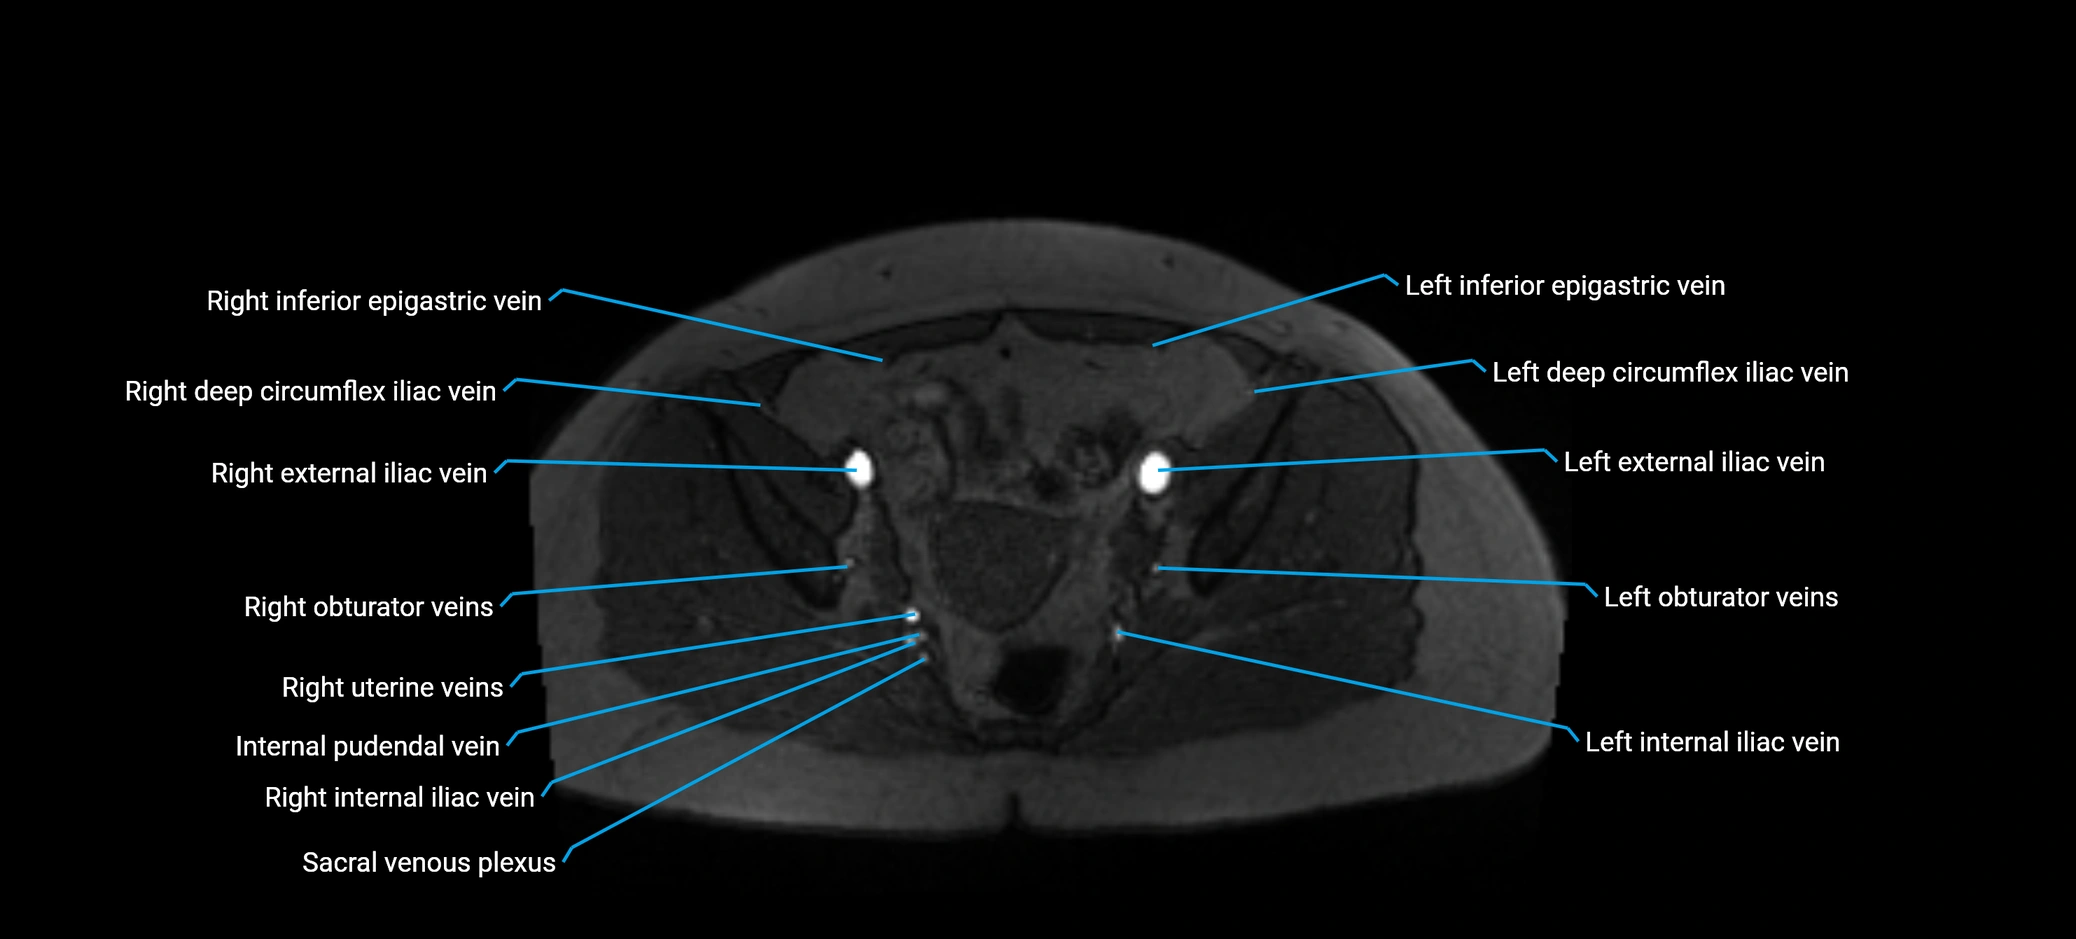

MRI image

image